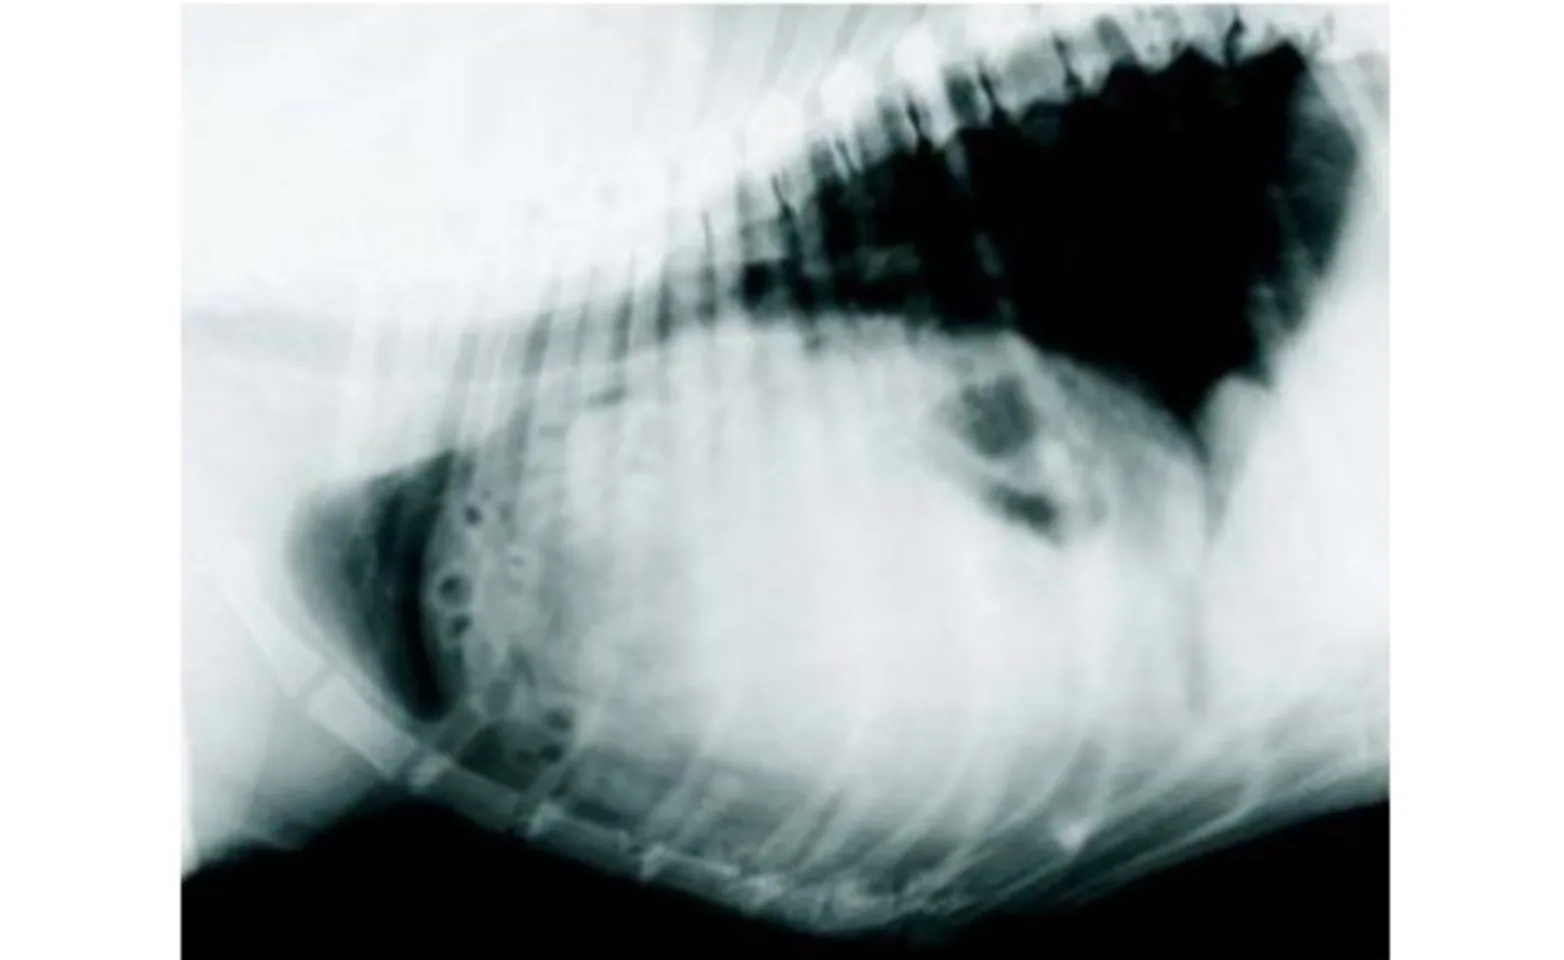

Many PPH are discovered as an incidental finding during routine thoracic and/or abdominal radiographs. Typical findings include enlargement of the cardiac silhouette and the presence of a soft tissue mass near the heart that is contiguous with the abdomen. If herniation of abdominal viscera has occurred, then bowel loops and/or liver can be seen adjacent to the heart on radiographs and sonogram. Because the thoracic cavity is not compromised, pneumothorax is not a typical finding and dyspnea is rarely observed.

Peritoneopercardial Hernias in Dogs and Cats Radiograph (Figure 1)